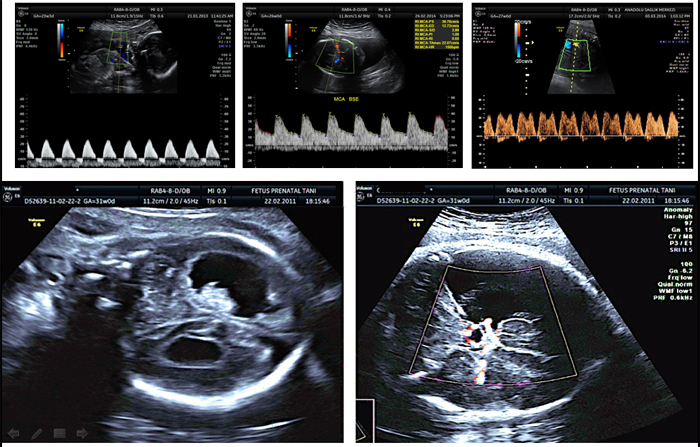

III. Trimester / Fetal büyüme – plasenta değerlendirmesi

Fetal Doppler incelemeleri

Umbilikal arter

Ductus venosus

Orta serebral arter

Plasenta incelemesi

Yerleşimi - görünümü

Servikse (doğum kanalı) yakınlığı

Damarlanma artışı

Plasenta arkasındaki myometrium yapısı

Umbilikal kord insersiyon yeri